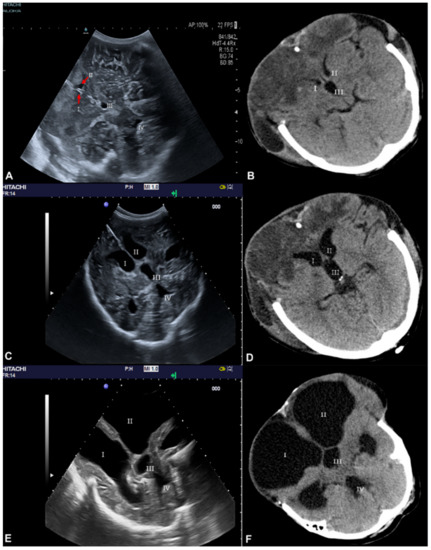

3.1. Ventricle Assessment

3.2. Cerebral Arteries